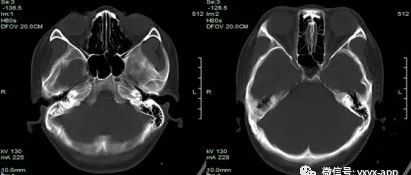

青年女性,头部外伤后2月感觉疼痛,请诊断!

医学影像  yxyx-app  医学影像APP,打造伴随医生快速成长的影像学习社区。与影像园(Xctmr.com)一起提供最全面的影像案例库、基础(解剖、病理、影像诊断)知识、影像技术及考题等,为医生提供最佳的医学影像参考。【所属科室】骨科【基本资料】患者,女,19岁,【主诉】头部拳击伤后2月,现感觉疼痛【体格检查】右顶部头皮肿胀,有波动感【影像图片】【讨论问题】...